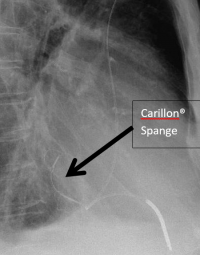

Schließt zum Beispiel die Mitralklappe, die Herzklappe zwischen dem linken Herzvorhof und der linken Herzhauptkammer nicht vollständig und beruht dieser unvollständige Schluss auf einer Vergrößerung der Herzhöhlen mit der Folge einer Vergrößerung des Durchmessers der Herzklappe, so kann bei ausgewählten Patienten durch eine Art Spange der Herzklappenschluss verbessert werden (Carillon® Mitral Contur System®). Diese Spange kann durch einen Kathetereingriff eingesetzt werden unter Umgehung einer Operation.